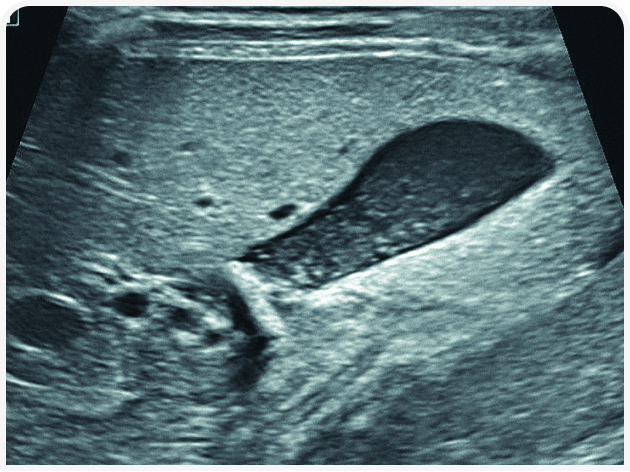

Решающее значение для диагностики и лечения в этом случае будет иметь ультразвуковое исследование органов брюшной полости (Рисунок 6). Диагностику триадита у кошек облегчают визуализация поджелудочной железы и определение толщины/архитектоники стенки кишечника; изменения в паренхиме печени по-прежнему остаются неспецифичными, но изменения в желчном пузыре, скорее всего, помогут установить диагноз. При нейтрофильном холангите у кошки результаты визуализации желчных путей могут оказаться нормальными, но во многих случаях стенка желчного пузыря будет утолщенной и неровной, даже зубчатой (Рисунок 7) (22). Возможны осадок (Рисунок 8) или наличие камней в желчном пузыре, поэтому желчевыводящие пути важно просмотреть до двенадцатиперстной кишки, чтобы исключить внепеченочную окклюзию желчных протоков. Во многих случаях общий желчный проток оказывается перекрыт. Возможен асцит, и в этом случае оправдано проведение аспирации и анализа состава жидкости.

Аспирация содержимого желчного пузыря (чрескожный холецистоцентез под контролем ультразвукового исследования) для цитологического и культурального исследования чаще всего позволяет поставить диагноз и подобрать лечение (Рисунок 9) (23). Если желчный пузырь при визуализации выглядит патологически (например, толщина стенки >1 мм, контур стенки неровный или зубчатый или выраженное гиперэхогенное содержимое (осадок; Рисунок 10), результаты цитологического исследования и бактериального посева, скорее всего, также будут отклоняться от нормы (22,24). Обратите внимание, что при аспирации существует риск разрыва стенки желчного пузыря и/или утечки содержимого с развитием желчного перитонита, но под контролем опытного специалиста УЗИ и при спокойном поведении/седации пациента проблемы возникают редко. Тем не менее если стенка желчного пузыря выглядит эмфизематозной, риск значительно возрастает и вместо аспирации следует рассмотреть возможность хирургического удаления или пробное лечение.

Аспирированная желчь может выглядеть совершенно нормальной или напоминать гнойный экссудат. При цитологическом исследовании обычно преобладают нейтрофилы в различных функциональных состояниях (т. е. в процессе нормальной дегенерации), иногда с внутриклеточными скоплениями бактерий (25). Неудивительно, что наиболее часто при посеве выявляют E. coli, реже – обширный список энтеральных и анаэробных микроорганизмов родов Enterococcus, Streptococcus, Klebsiella, Actinomyces, Clostridium, Bacteroides, Pseudomonas, Staphylococcus, Pasteurella, а также Salmonella enterica серотип Typhimurium.